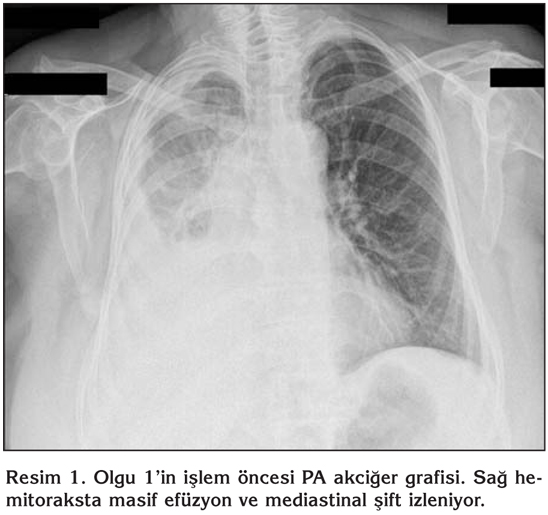

Bilinen hipertansiyon d???nda rahats?zl??? olmayan hastan?n bir ay ?nce ba?layan ?ks?r?k ve nefes darl???, sa? yan a?r?s? ?ikayetleri mevcutmu?. Sa? plevral ef?zyonu saptanan hastaya uygulanan torasentez sonras? eks?da vasf?nda plevral mayii elde edilmi?. Sistemik muayenesinde sa? akci?er alan?nda solunum seslerinin al?namamas? ve ayn? alanda perk?syonla matite al?nmas? d???nda bulgu saptanmad?. Vital bulgular? normal s?n?rlar i?indeydi. Toraks bilgisayarl? tomografi (BT) incelemesinde mediastinal yap?lar k?smen sola deviye, sa? ?st ve alt paratrakeal lokalizasyonlarda en b?y??? 23 mm ?ap?nda multip lenfadenomegaliler izlenmekteydi. Sol alt paratrakeal ve subkarinal lokalizasyonlarda da ?ap? 1 cm civar?nda lenfadenomegaliler mevcuttu. Sa? hemitoraksta masif plevral ef?zyon izlenmekteydi ve sa? akci?er tamamen atelektazikti. Resim 1 ve 2'de olgunun s?ras?yla i?lem ?ncesi ve sonras? PA akci?er grafileri g?r?lmektedir.

Resim 1

Resim 2

Hastan?n plevra s?v?s? eks?da karakterinde ve lenfosit hakimiyetinde saptand?. Terap?tik torasentez yap?ld?. Hastaya tan?sal ama?l? semirijid torakoskopi yap?ld?. Pariyetal plevra ?zerindeki nod?llerden yeterli say?da biyopsi ?rnekleri al?nd?. Hastada i?lem sonras? hafif cilt alt? amfizemi d???nda herhangi bir komplikasyon g?zlenmedi. Ertesi g?n t?p torakostomisi sonland?r?ld?. Al?nan biyopsi sonucu imm?nhistokimyasal ?al??mada t?m?r h?creleri TTF-1 (pozitif), CEA (pozitif), Ber Ep 4 (negatif), Sitokeratin 7 (pozitif), Sitokeratin 20 (negatif), Mezotelin (pozitif), Kalretinin (negatif) imm?nreaktivite g?sterdi ve akci?er k?kenli adenokarsinom ile uyumlu olarak saptand?.